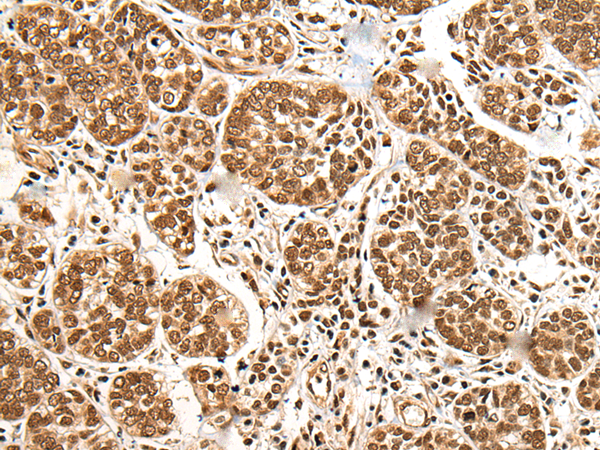

分类: 科研抗体货号: P02407别名: hSAD1应用: IHC反应种属: Human, Mouse, Rat